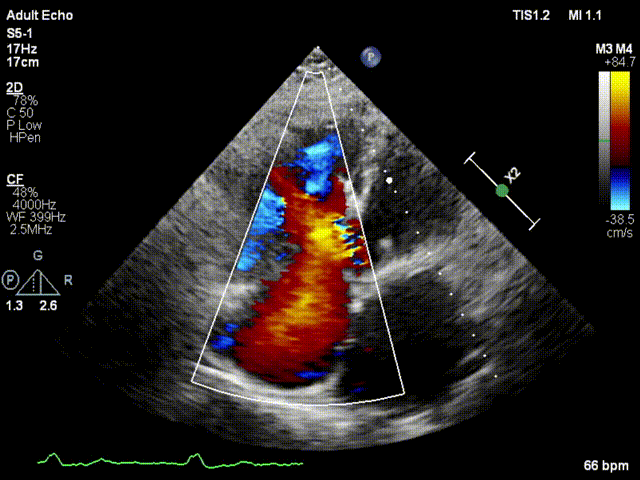

手术在患者全麻状态下进行,采用经右侧颈静脉作为入路,将装载有人工瓣膜的输送器缓慢推送至右心房;并在经食道超声和DSA的引导下小心调整输送器角度,将输送器送入右心室;逐步释放瓣膜锚定装置和盘片,调整瓣膜位置后,锚定瓣膜完成植入。术后右房压明显下降,从术前的25/10(16) mmHg降至术后即刻的12/7(10) mmHg,术后超声提示人工三尖瓣同轴性良好,固定牢固,无反流及瓣周漏手术室即刻拔除气管插管。

术后超声1

图片

术后超声2

术后超声3